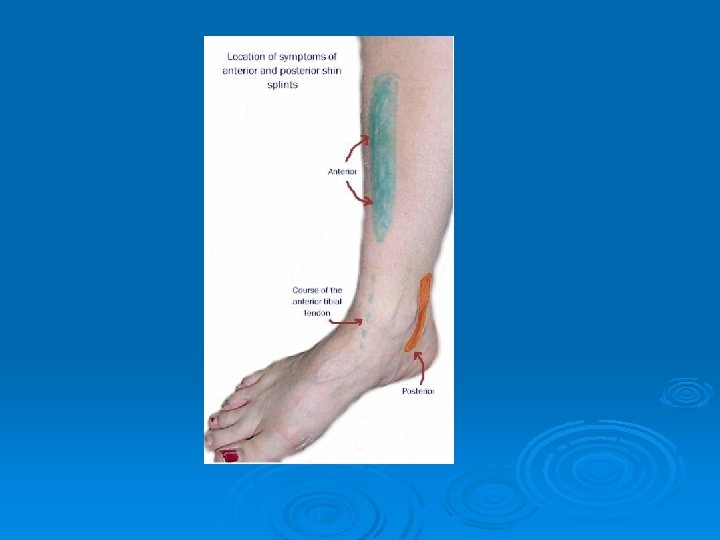

Lower Leg Problems Ø “Shin Splints”: l Ø MX: l Ø constant pounding associated with running S/S: l Ø catch all term related to lower leg pain. sharp pain in lower leg around medial/lateral aspect of lower leg and connective tissue between tibia and fibula TX: l RICE (cold whirlpool), heal lift, arch support, shoes, change running surface